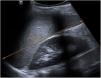

The World Health Organization defines the multisystem inflammatory syndrome in children (MIS-C) as a new syndrome reported in patients aged <19 years old who have a history of exposure to SARS-CoV-2. The onset of this syndrome is characterized by persistent fever that is associated with lethargy, abdominal pain, vomiting and/or diarrhea, and, less frequently, rash and conjunctivitis. The course and severity of the signs and symptoms vary; in some children, MIS-C worsens rapidly and can lead to hypotension, cariogenic shock, or even damage to multiple organs. The characteristic laboratory findings are elevated markers of inflammation and heart dysfunction. The most common radiological findings are cardiomegaly, pleural effusion, signs of heart failure, ascites, and inflammatory changes in the right iliac fossa. In the context of the current COVID-19 pandemic, radiologists need to know the clinical, laboratory, and radiological characteristics of this syndrome to ensure the correct diagnosis.

El síndrome inflamatorio multisistémico pediátrico vinculado a la COVID-19 (SIM-PedS) es, según la Organización Mundial de la Salud, un nuevo síndrome descrito en pacientes menores de 19 años con historia previa de exposición a SARS-CoV-2. La presentación inicial de este síndrome se caracteriza por fiebre persistente que asocia debilidad, dolor abdominal, vómitos y/o diarrea. Menos frecuentemente los pacientes pueden presentar también erupción cutánea y conjuntivitis. El cuadro clínico tiene expresividad y evolución variables, por lo que algunos pacientes pediátricos afectados pueden empeorar rápidamente, desarrollando desde hipotensión y shock cardiogénico a daño multiorgánico. Los hallazgos analíticos característicos del síndrome consisten en elevación de marcadores inflamatorios y disfunción cardíaca. Los hallazgos radiológicos más frecuentes son cardiomegalia, derrame pleural, signos de insuficiencia cardíaca, ascitis y cambios inflamatorios en la fosa ilíaca derecha. En la pandemia actual por COVID-19 es necesario que el radiólogo conozca las características clínico-analíticas y radiológicas de este síndrome para realizar un correcto diagnóstico.